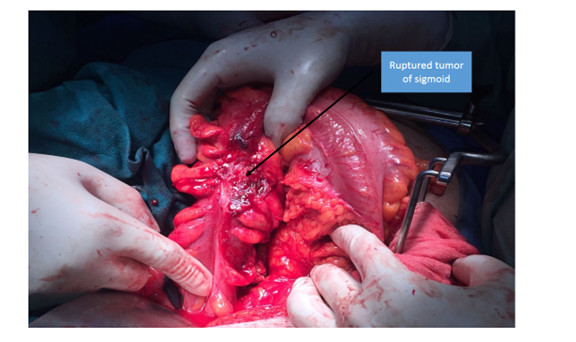

A 67 years old male patient who was known to have chronic ulcerative colitis for 18 years was admitted with complaints of pain abdomen, distention and […]